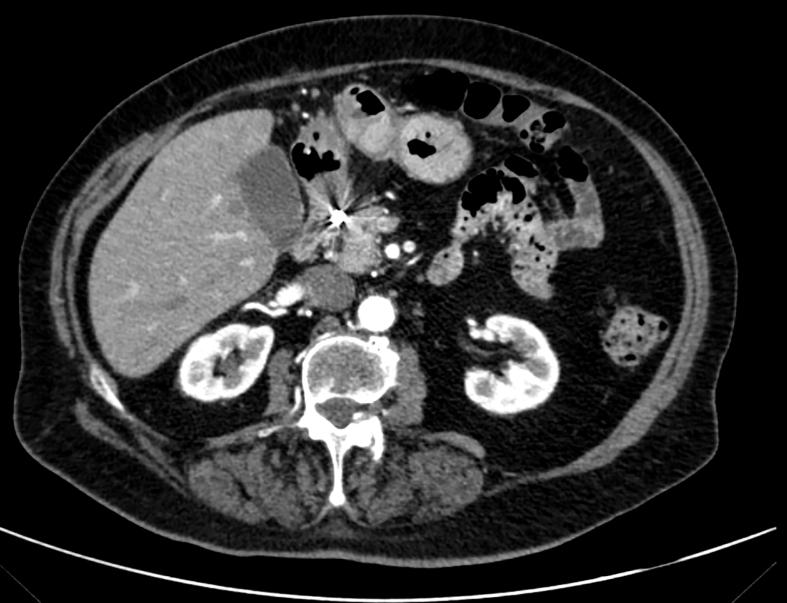

PRESENTATION OF CASE

We report the case of an 82-years-old female presenting with abdominal pain and hematemesis. Upper gastrointestinal endoscopy retrieved a large duodenal mass and subsequent CT scans identified a large GAA with contrast extravasation. Endovascular procedure included selective arteriography, microcatheterization, and embolization.

我们报告了一例82岁女性,表现为腹痛和呕血。上消化道内镜检查发现十二指肠有一个大肿块,随后的CT扫描确定为一个大的GAA并伴有造影剂外渗。血管内治疗包括选择性动脉造影、微导管插入和栓塞。